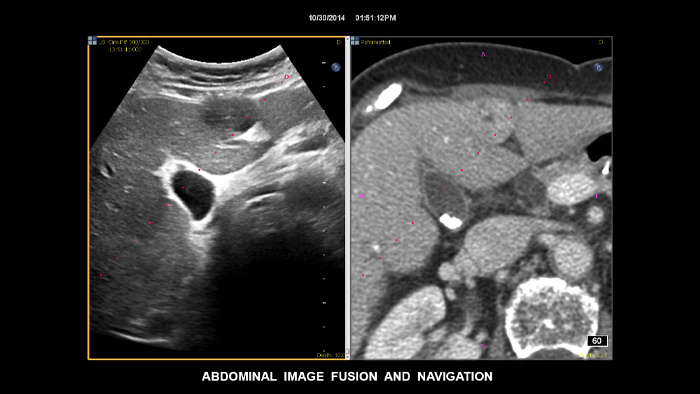

Tome decisiones fiables incluso en casos diagnósticos complejos gracias a las funciones de navegación guiada por aguja y fusión de imágenes de Philips. El flujo de trabajo agilizado permite a los médicos conseguir una fusión rápida y efectiva de imágenes TC/RM/PET mediante ecografía en tiempo real, mientras que la navegación guiada por aguja permite guiar la biopsia en lesiones pequeñas o de difícil acceso.2.